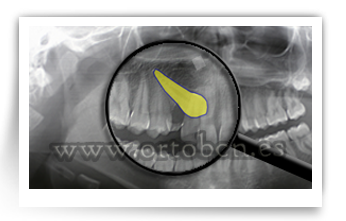

Ullal ectopic

Ectòpia